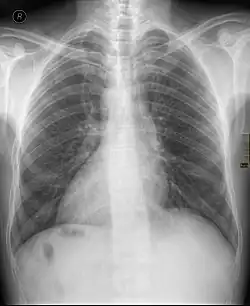

| Chest X ray of a person with dextrocardia situs inversus showing the cardiac apex pointing towards right | |

Dextrocardia (from Latin dextro 'right hand side' and Greek kardia 'heart') is a rare congenital condition in which the apex of the heart is located on the right side of the body, rather than the more typical placement towards the left.[1] There are two main types of dextrocardia: dextrocardia of embryonic arrest (also known as isolated dextrocardia)[2] and dextrocardia situs inversus. Dextrocardia situs inversus is further divided.

Dextrocardia situs inversus refers to the heart being a mirror image situated on the right side. For all visceral organs to be mirrored, the correct term is dextrocardia situs inversus totalis.[5][6]